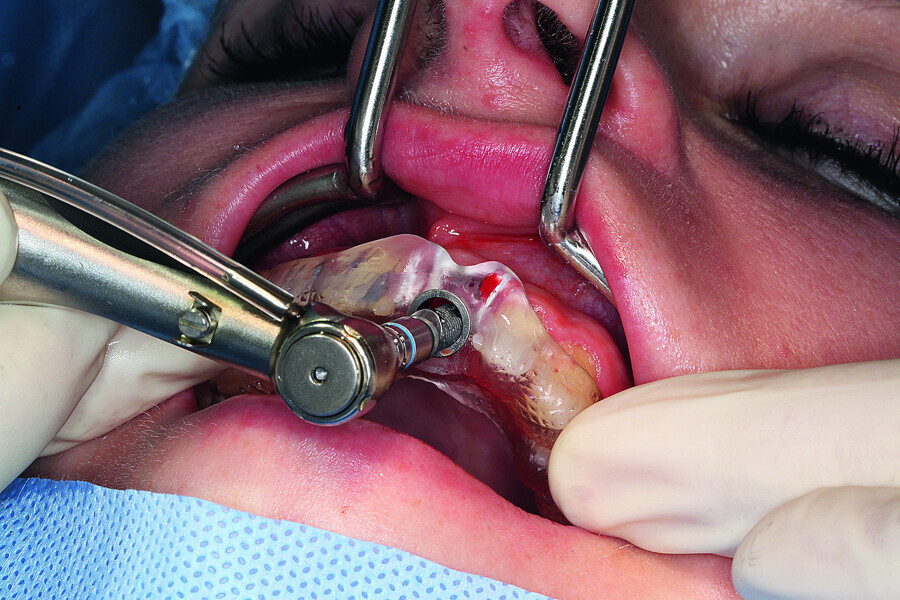

Fig. 7: Gentle extraction preserving the vestibular lamina.